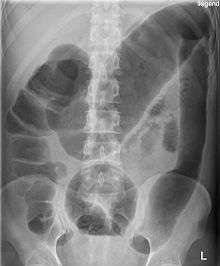

Toxic megacolon (megacolon toxicum) is an acute form of colonic distension.[1] It is characterized by a very dilated colon (megacolon), accompanied by abdominal distension (bloating), and sometimes fever, abdominal pain, or shock.

There may be signs of septic shock. A physical examination reveals abdominal tenderness and possible loss of bowel sounds. An abdominal radiography shows colonic dilation. White blood cell count is usually elevated. Severe sepsis may present with hypothermia or leukopenia.